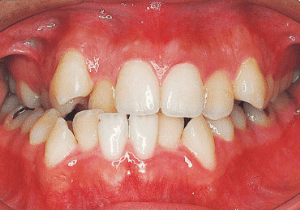

2 After treatment 2-10-’99

22 After treatment 2-10-’99 17 years 7 month

23 After Retention 1-22-’01 19 years 6 month

Although early treatment improved the slight deviation observed during the deciduous dentition stage, it became apparent that the deviation increased with age, eventually exceeding the limits of treatment. This appears to be an innate deviation, and the developmental pattern observed in this case seems to disregard the occlusion. Four first premolars were extracted (15), crowding was corrected and space closure was performed (16), and surgical intervention improved the deviation (17).